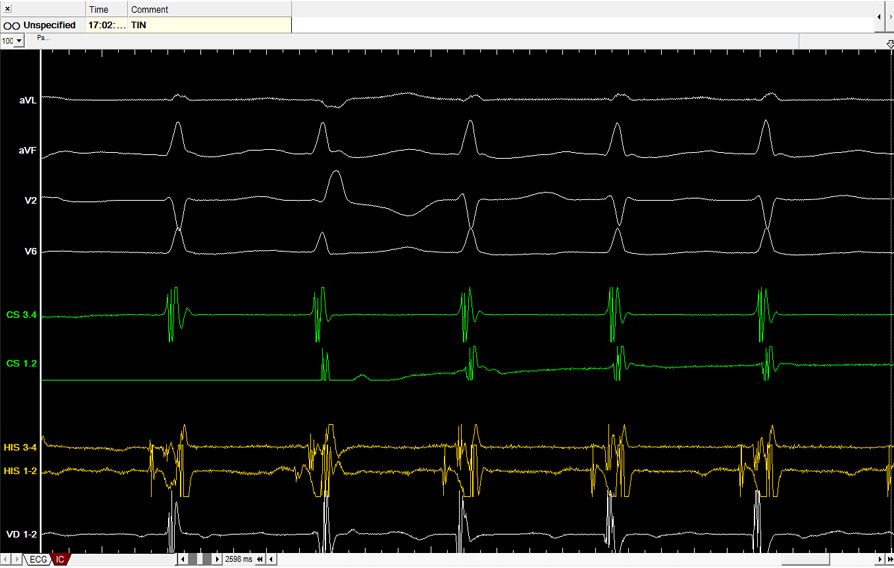

Bajo este nombre se agrupan varios tipos de arritmias que se caracterizan por tener como tratamiento de elección la ablación mediante cateterismo, dado que el éxito de dicho procedimiento es mayor del 90% y evita a los pacientes tener que tomar medicación antiarrítmica.

Entre ellas se encuentran la taquicardia intranodal y la taquicardia mediada por vías accesorias (Wolff-Parkinson-White), que se caracterizan por episodios repetidos y bruscos de palpitaciones, habitualmente en pacientes jóvenes o de edad media. También se agrupan con este nombre la taquicardia auricular y el flutter auricular.